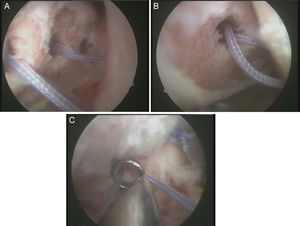

No es estrictamente necesario que reproduzcamos un enganche de la lesión de Hill-Sachs inversa para decidir realizar el remplissage inverso. Con la óptica en el portal anterosuperolateral liberamos el tendón del subescapular, su cara anterior y posterior. Preparamos el lecho óseo de la cabeza humeral, extirpando todo el tejido fibroso de la lesión de Hill-Sachs inversa, con el sinoviotomo, la fresa de hueso o periostotomos, hasta obtener hueso sangrante. Entonces desde el portal anterior, insertamos los implante en el defecto óseo (en el caso 1 un 5,5 Healix BR [DePuy Mitek, Raynham, MA] con 2 suturas UHMWPE [Orthocord; DePuy Mitek]) en el tercio superior y en la zona más medial del defecto (fig. 5), y en el caso 2 insertamos 2 Gryphon BR Healix BR (DePuy Mitek, Raynham, MA) con 2 suturas UHMWPE (Orthocord; DePuy Mitek), uno inferior y otro superior en la zona más medial del defecto óseo. Recuperaremos las suturas desde un portal anterosuperior accesorio y con una pinza para atravesar el tendón (Penetratror DePuy Mitek, Raynham, MA) a través del portal anterior, atravesamos el tendón del subescapular y recuperamos las suturas. Daremos puntos colchoneros, uno inferior y otro superior, para conseguir un buen contacto del tendón con el hueso, separando los puntos entre 1 y 2cm (fig. 6). Podemos ayudarnos con un empujanudos a través del portal anterosuperior accesorio para el manejo y recuperación de las suturas, acercándolas a la boca de la pinza penetrator, tratando de no mover en exceso la pinza una vez atravesado el tendón, para evitar lesionar el tendón y el cartílago. Manteniendo el brazo en 35-40° de rotación interna anudamos primero el punto inferior y luego el superior (figs. 7 y 8).

Caso 2, hombro izquierdo. A. Visión desde el portal ASL de la cara posterior del subescapular con los 2 implantes en la parte inferior y superior del defecto óseo. B. Imagen tras el anudado del punto más inferior. C.

Imagen de la cara anterior del subescapular tras el anudado del segundo punto.